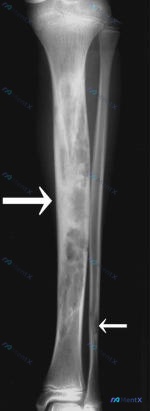

- X 光(14 岁及当前):胫骨骨干大范围溶骨性骨质破坏,呈膨胀性改变,骨皮质变薄,内部可见骨纹理消失及残留骨嵴(多房样改变)。侧位片可见胫骨前侧软组织轮廓向外膨出。